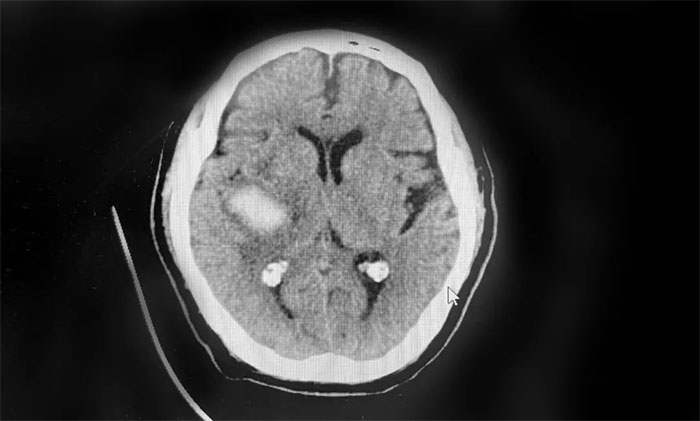

患者徐老伯(化名)今年73岁。今年2月,其在打乒乓时,突感头晕伴左侧肢体活动不利,送医至就近医院。经查,患者右侧基底节出血、蛛网膜下腔出血,给予脱水降颅压等对症支持治疗。

▲ 患者右侧基底节出血、蛛网膜下腔出血